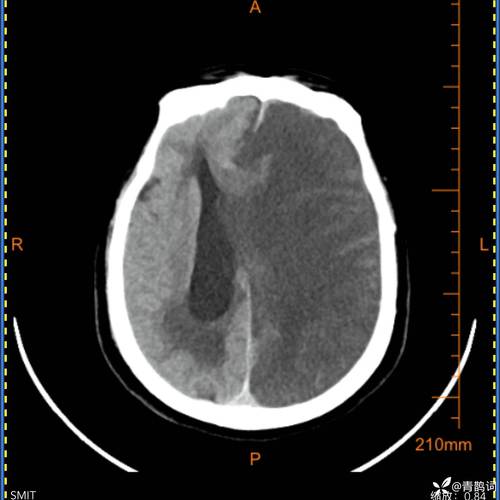

大面积:这是最关键、也是最严重的一点,它意味着堵塞的血管主干非常粗大,导致其供应的整个脑叶(如整个额叶、颞叶、顶叶,或它们的组合)都发生了梗塞,梗死的脑组织范围很广,通常梗塞体积会超过50-80毫升,甚至更多。

- 意识障碍:这是大面积脑梗最危险的表现,患者可能出现嗜睡、昏睡、甚至昏迷,因为大面积脑水肿会压迫脑干等生命中枢,影响呼吸和心跳。

- 颅高压症状:剧烈头痛、喷射性呕吐、血压升高等,这是因为梗死的脑组织肿胀,导致颅内压力急剧增高。

- 控制颅高压:使用高渗性脱水剂(如甘露醇)来减轻脑水肿,防止脑疝形成(这是致死的主要原因)。